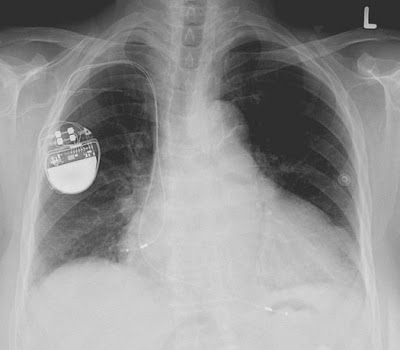

Pacemaker-hacking feels like a Hollywood plot. Assassinate someone by taking over the medical device that controls his heart? Surely that isn't possible in the real world.

Actually, it's totally possible. Last year, a researcher demonstrateda pacemaker hack in Australia, with a virus that could conceivably spread from one person to every electronically assisted heart within 30 feet.

Probably limited to assassination targets. Think: high-profile people, who have pacemakers. It would be an elaborate attack, though, since you need more than just an internet connection to pull it off. Odds are that anyone interested in doing this could get a bomb or a pistol to the target cheaper and faster. This is Hollywood not because it's impossible, but because it's not very efficient.